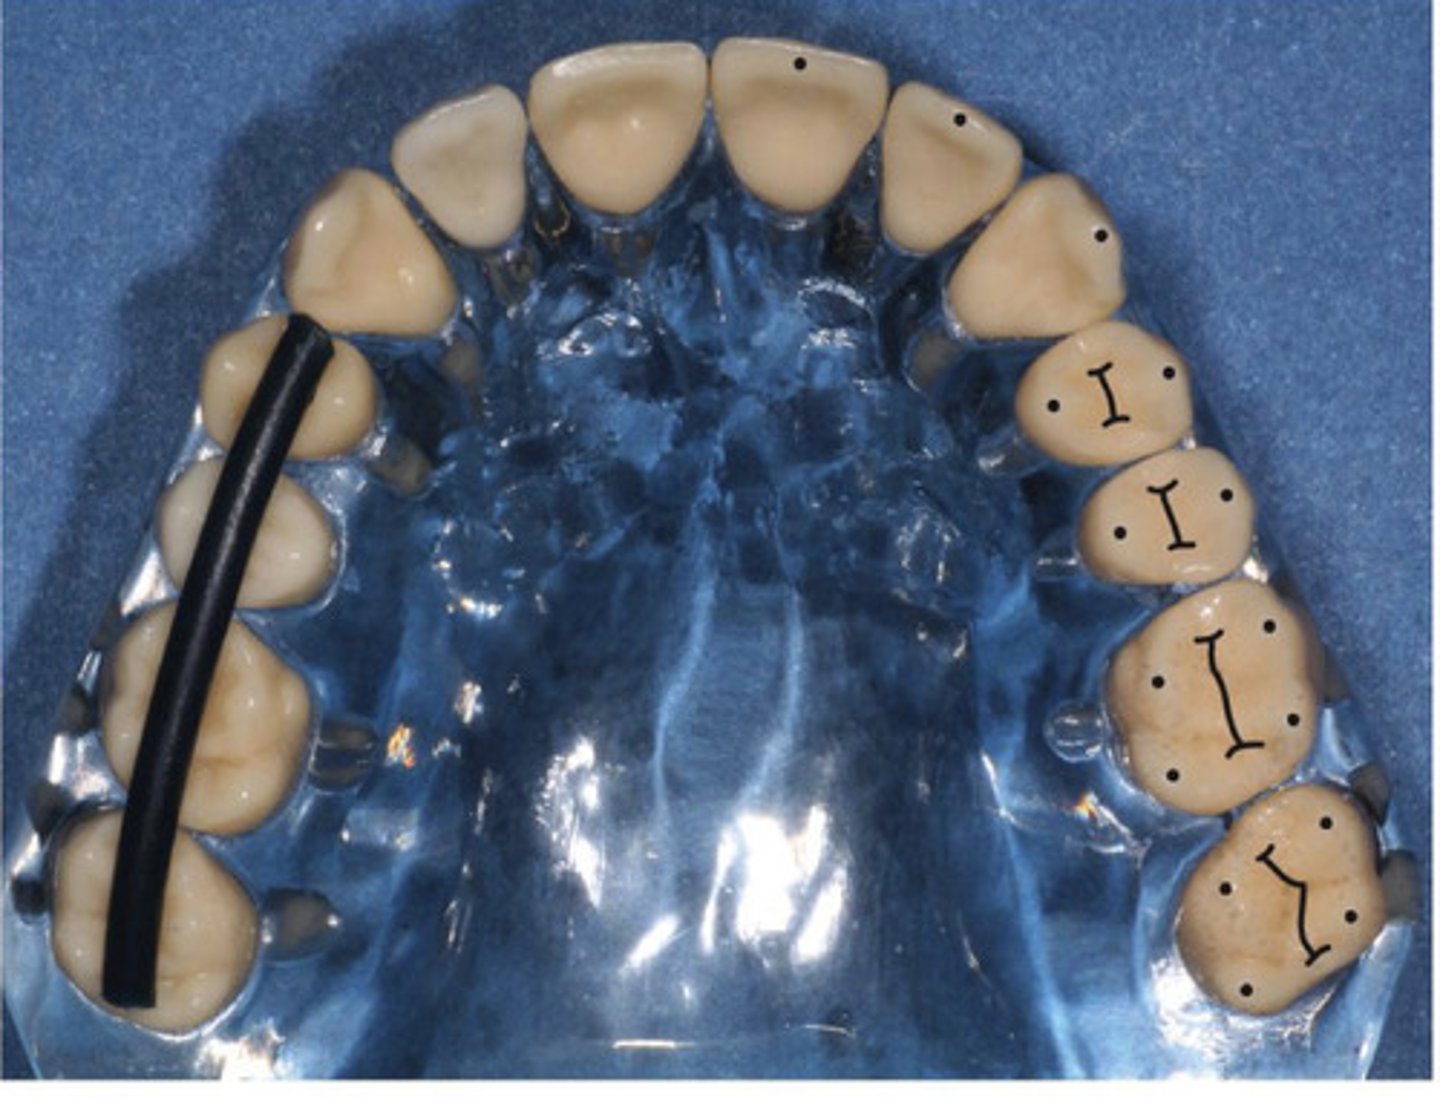

When we talk about teeth, what is the order we name them in?

arch --> quadrant --> position --> class

-maxillary/mandibular, right/left, distance from midline, tooth

What is the occlusal crown outline?

Outer outline of the entire tooth crown from the occlusal view

What is the ideal alignment of teeth?

all buccal and lingual cusp tip surfaces follow imaginary parabolic lines that are parallel to one another